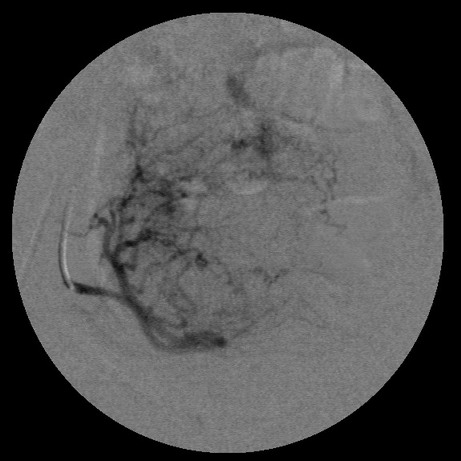

女,35岁,子宫多发肌瘤

子宫动脉增粗,分支数量增多,迂曲,染色明显并排空延迟